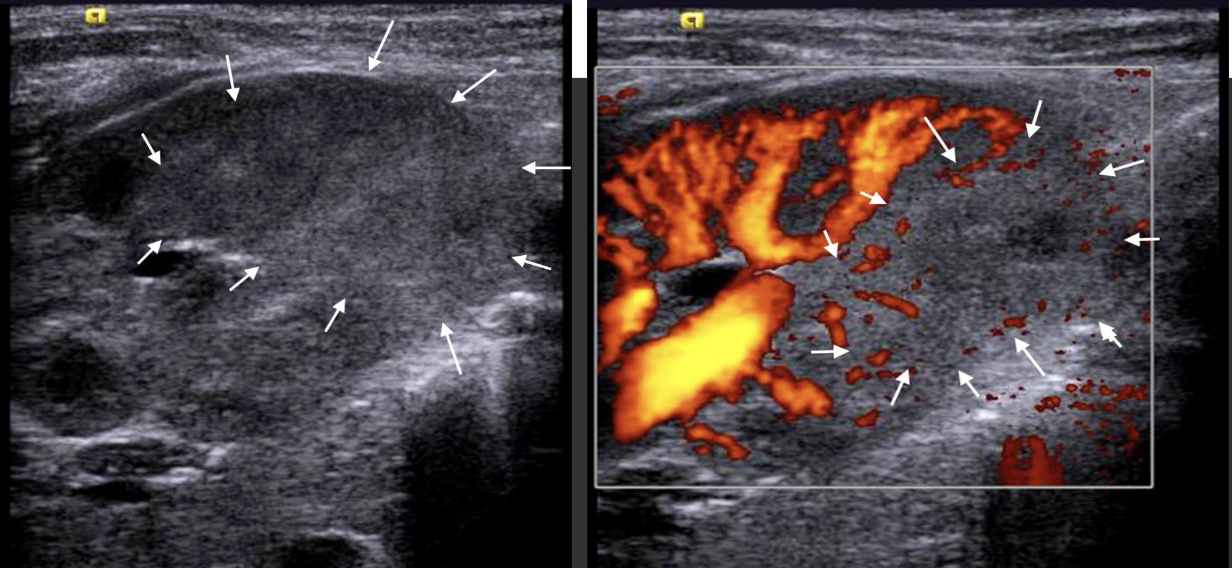

Nephroblastoma (Wilm’s Tumor) → 2nd most common peds abdominal cancer

clinical hx: 2-5 years, unilateral, Beckwidth-Wiedmann

s/sx: abdominal swelling, abdominal pain

2D US: vascular involvement, large solid mass, distorts renal cortex, sinus, pyramids and contour, hydronephrosis, extension into renal vein, IVC, contralateral kidney, homogenous to complex, calcifications, well-defined

color doppler: hypovascular/vascular

DDX: neuroblastoma, hepatoblastoma